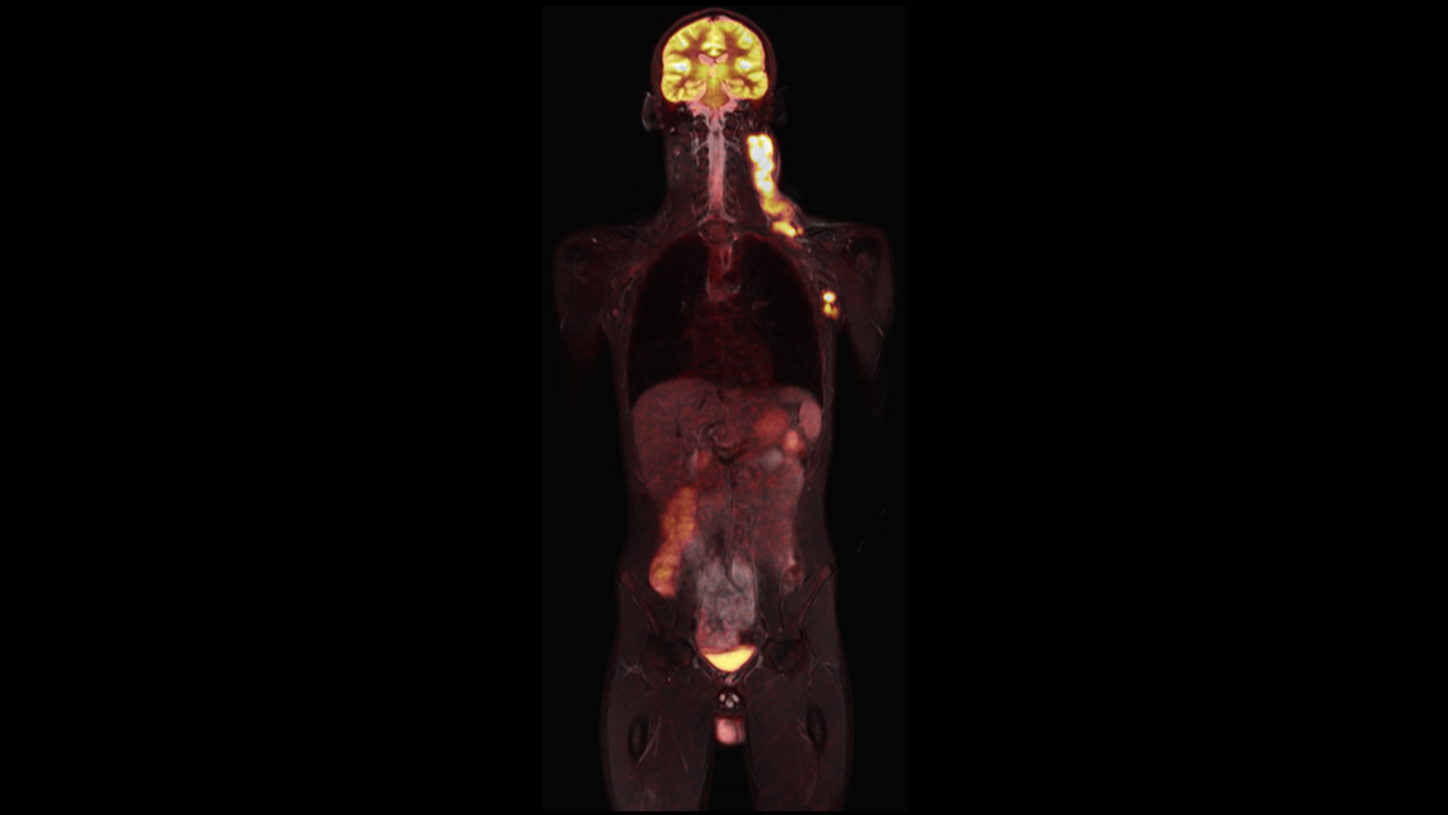

Image courtesy: ZEMODI, Bremen, Germany1

BIOGRAPH One is designed to support one patient-centric pathway to personalized care. By seamlessly integrating PET and MR into one comprehensive exam, it will support clinicians from diagnosis and staging, through a personalized therapy decision to regular therapy assessments to excel precision and support one streamlined approach.

BIOGRAPH One is designed to excel in PET/MR precision to support confident diagnostic decisions. Featuring the Optiso UDR Pro detector with the largest 35 cm axial FOV2 in PET/MR, it is designed to enable comprehensive capture with excellent sensitivity and ultra-fast TOF3 in real time – delivering clear, detailed images.